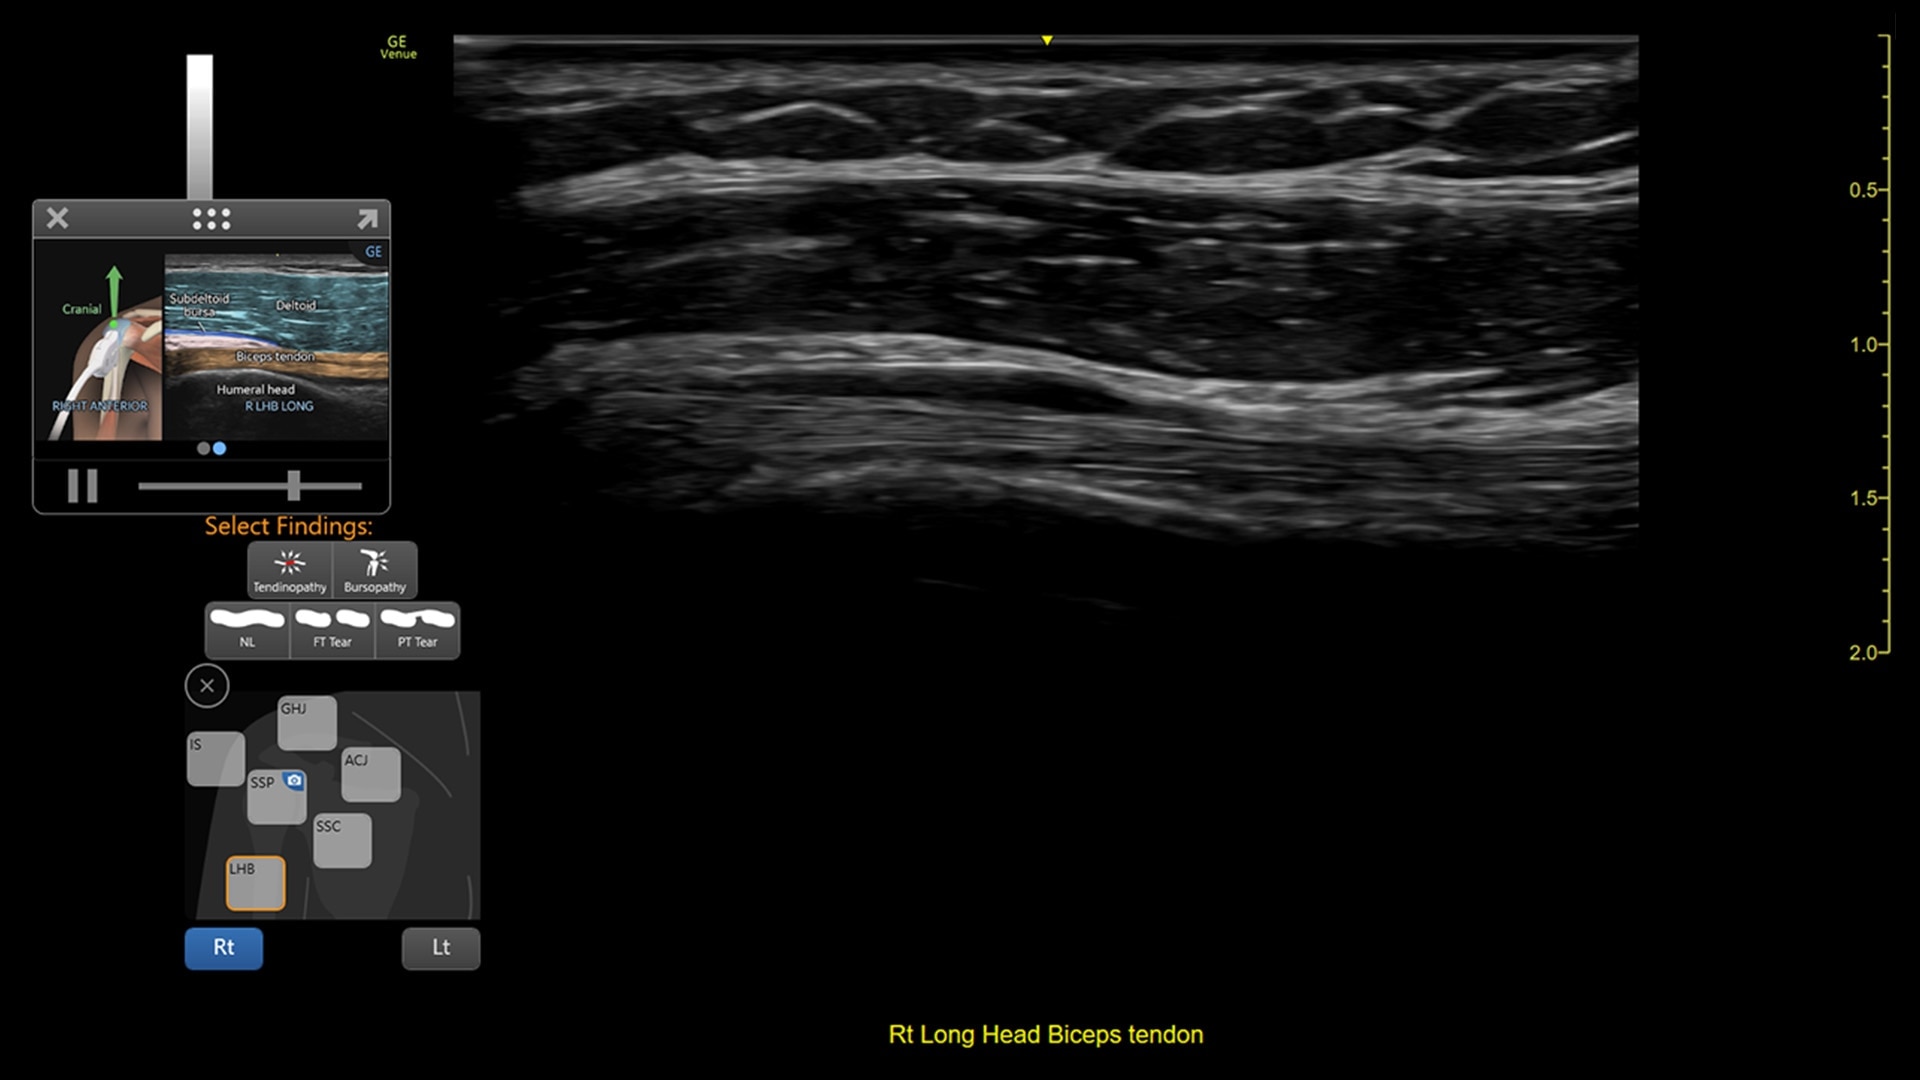

Venue Coach MSK

Simplifying MSK scans

This easy-to-use exam documentation tool assists users through exams by providing reference images and anatomy markups. Multiple anatomical areas and helpful video tutorials help clinicians to acquire the scans they need.

Focus areas include:

• Shoulder

MSK Diagrams: Simplifies documentation and assists the clinician in follow up for patients. No need to manually type findings—you can simply assign a label from a pre-populated list that correlates with the images. Get a single view diagram with one click image storing, keep track of assessments and show trends in response to therapy.

Reference Image: Reference image provides anatomy mark-ups to assist novice users in scanning the correct anatomy